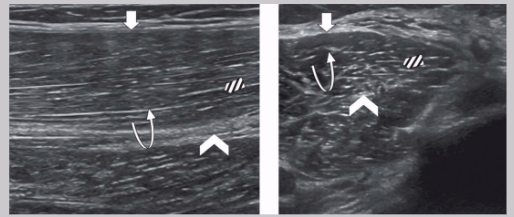

Nerve appearance on US

Nerve fiber enclosed by hyperechoic epineurium

LAX

“Railroad” or “tram track”

Hypoechoic nerve fibers divided by hyperechoic perineurium

SAX

“Honeycomb” pattern

Hypoechoic nerve fibers surrounded by hyperechoic perineurium